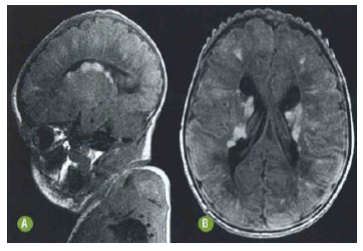

A seguinte ressonância magnética encefálica de neonato corrobora para o diagnóstico de esclerose tuberosa, tendo como principal achado

A

cistos periventriculares.

B

nódulos subependimários.

C

hemoventrículo.

D

hidrocefalia.

E

gliomas do teto mesencefálico